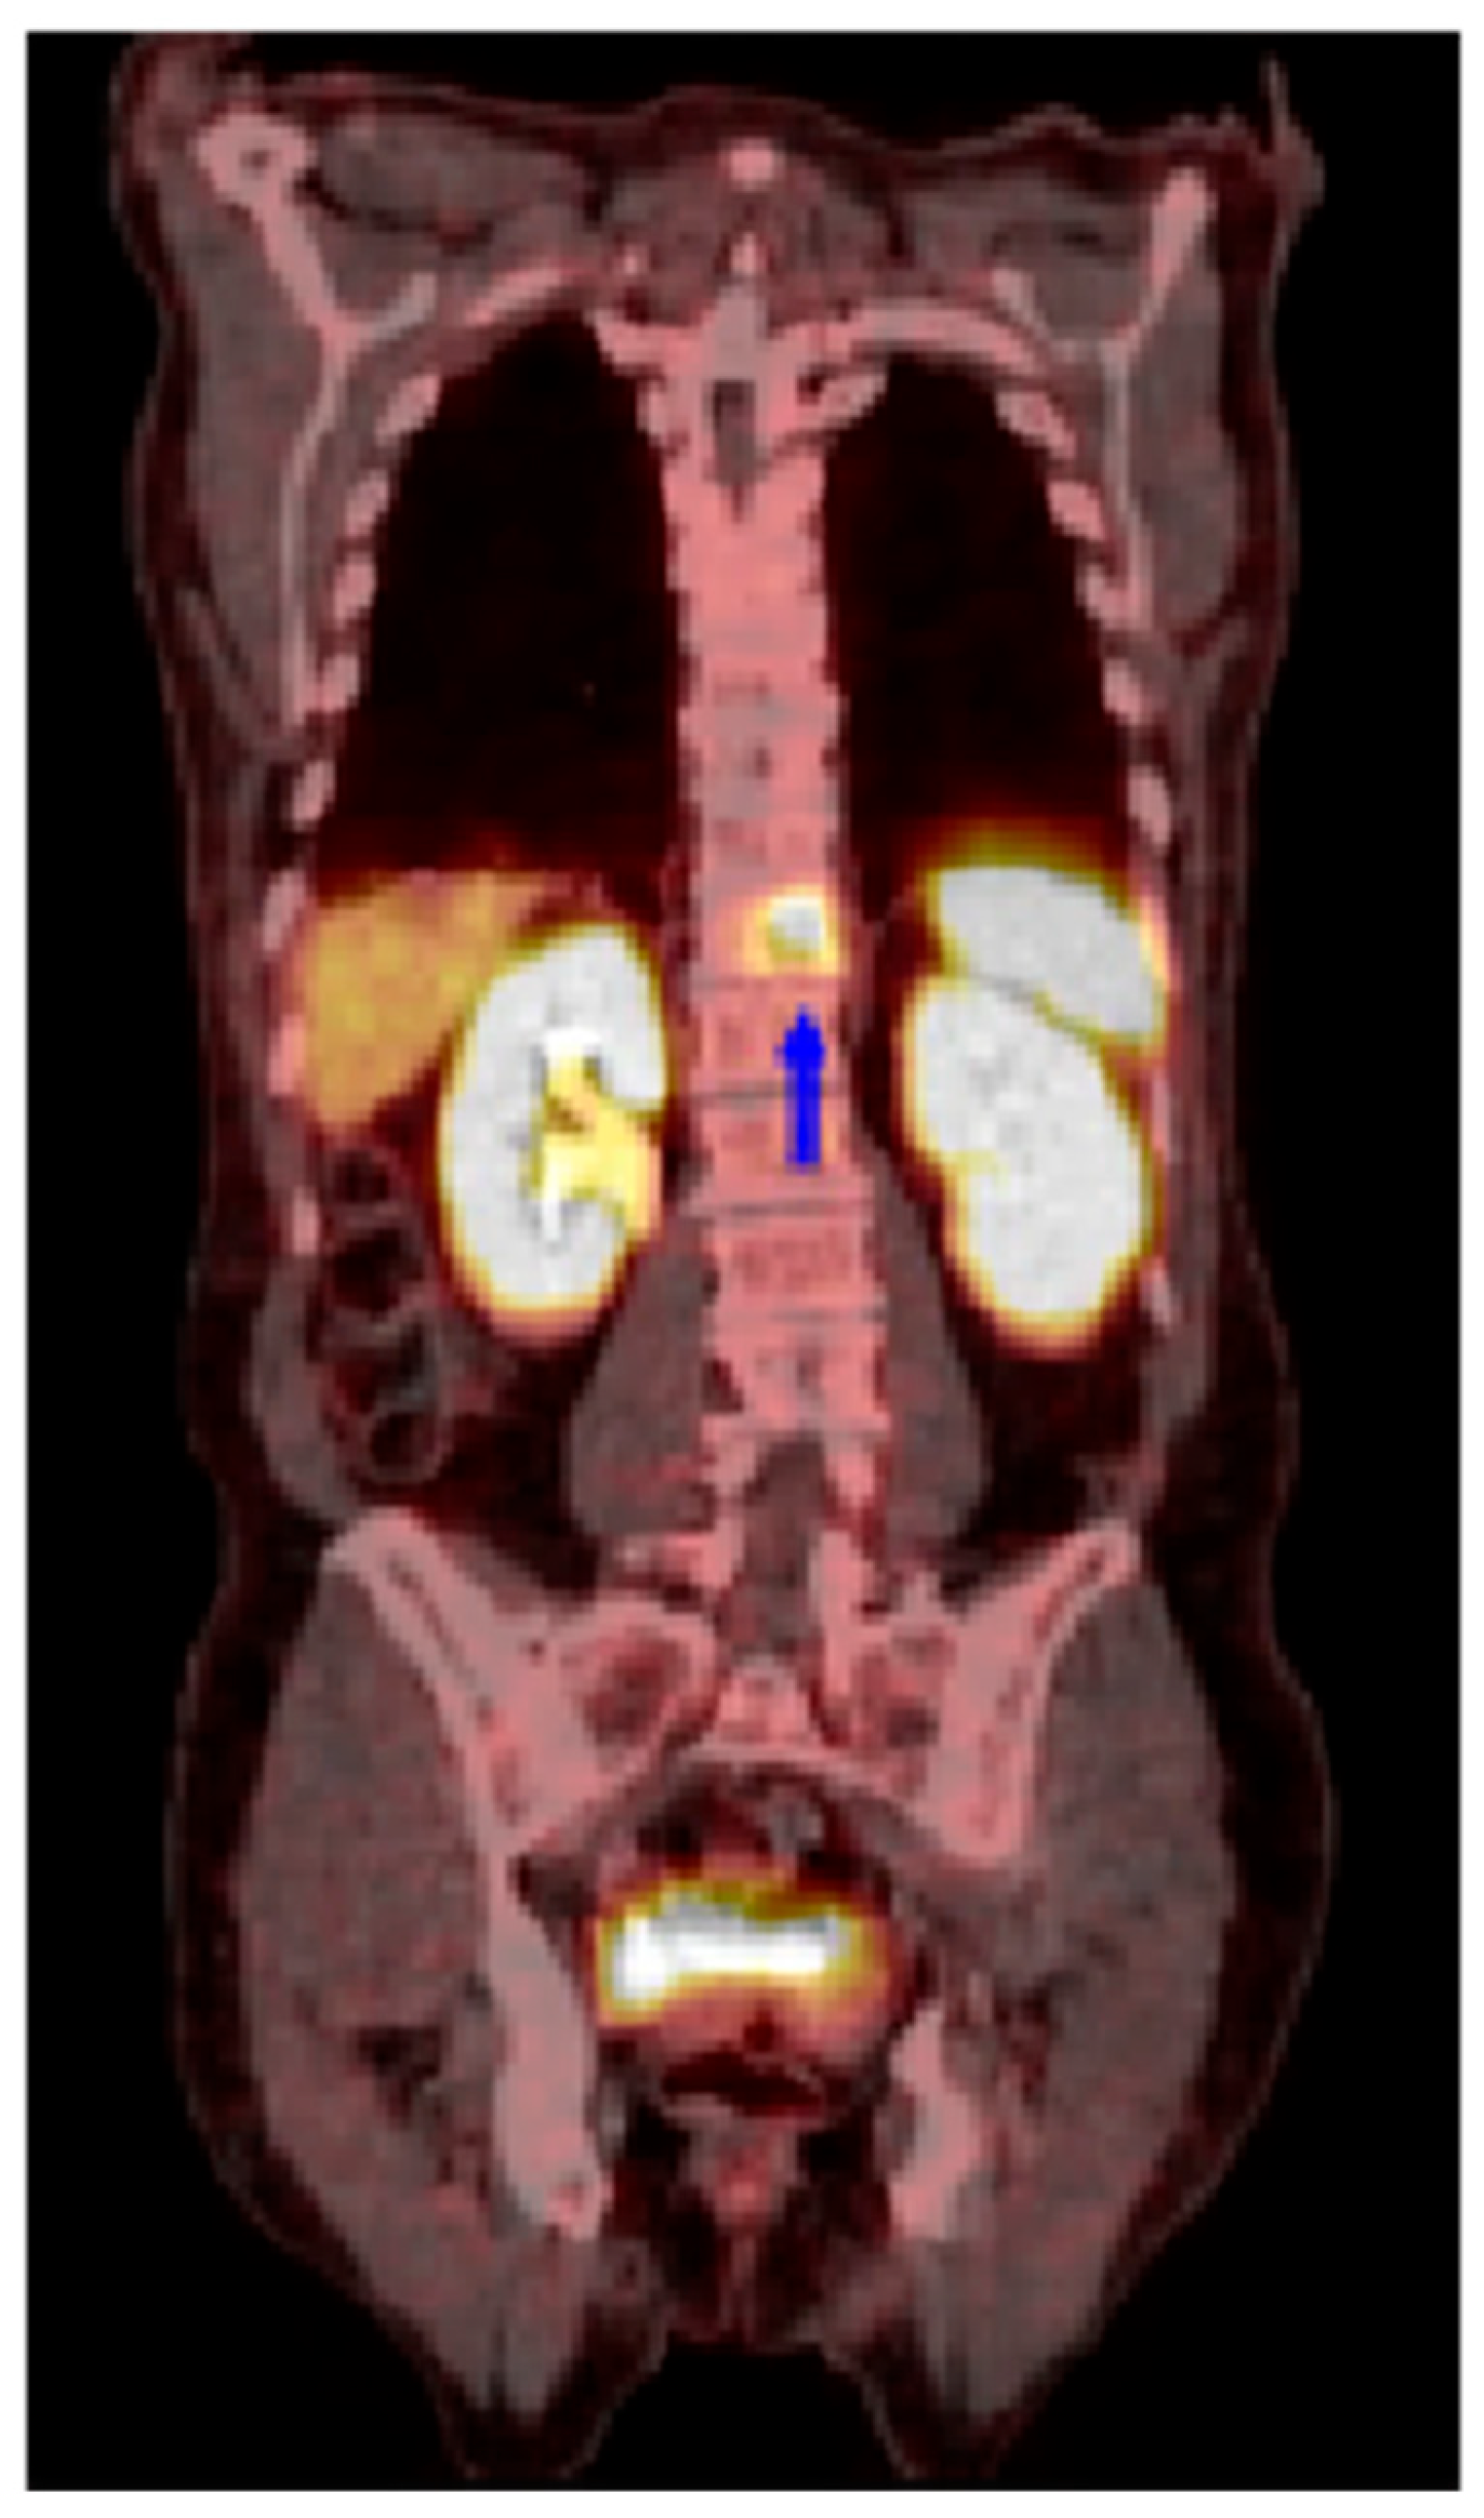

SSTR2-Targeted Theranostics in Hepatocellular Carcinoma

Momeny, M.; AghaAmiri, S.; Hernandez Vargas, S.; Acidi, B.; Ghosh, S.C.; Bateman, T.M.; Adams, J.T.; Khalaj, V.; Kaseb, A.O.; Tran Cao, H.S.; et al. SSTR2-Targeted Theranostics in Hepatocellular Carcinoma. Cancers 2025, 17, 162. https://doi.org/10.3390/cancers17020162